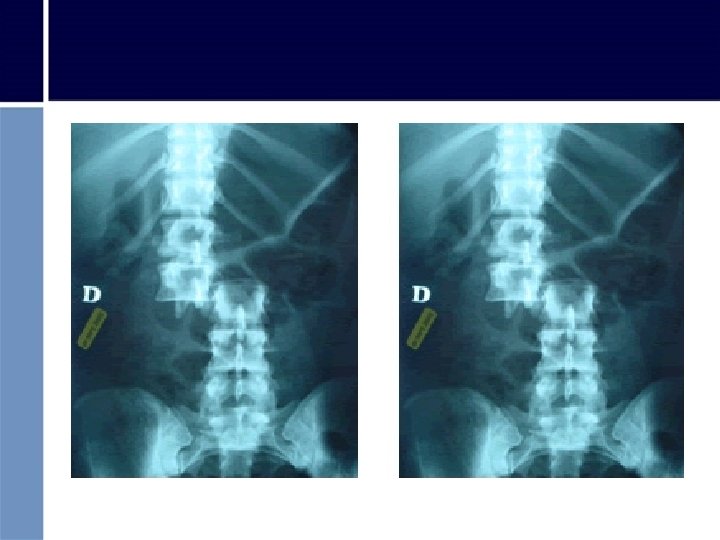

• FRACTURA COLUMNA VERTEBRAL: - Dolor intenso - Disminución o pérdida de sensibilidad y movilidad de las extremidades

Primeros Auxilios en ambas situaciones • Conducta PAS • Priorizar • INMOVILIZACIÓN: no tocar ni mover al herido • Si está consciente: debe permanecer inmóvil • Permanecer a su lado, controlando conciencia, respiración y pulso • Abrigar a la víctima • En caso de tener que movilizar al paciente: evitar movimientos que agraven o provoquen una lesión medular • Traslado urgente

Movilizar sin provocar más daño • No provocar flexión de la espalda • No doblar nunca al herido, no hacerlo sentar • No transportar tomándolo de las axilas ni rodillas • No flexionar ni girar la cabeza • Realizar movimientos imprescindibles y siempre formando un BLOQUE RÍGIDO “cabeza-cuello-extremidades”. Movimientos suaves y sincronizados • Trasladar sobre superficie dura, de cúbito supino, rellenando huecos. • Si no se dispone de estos medios: movilizar sólo si es imprescindible